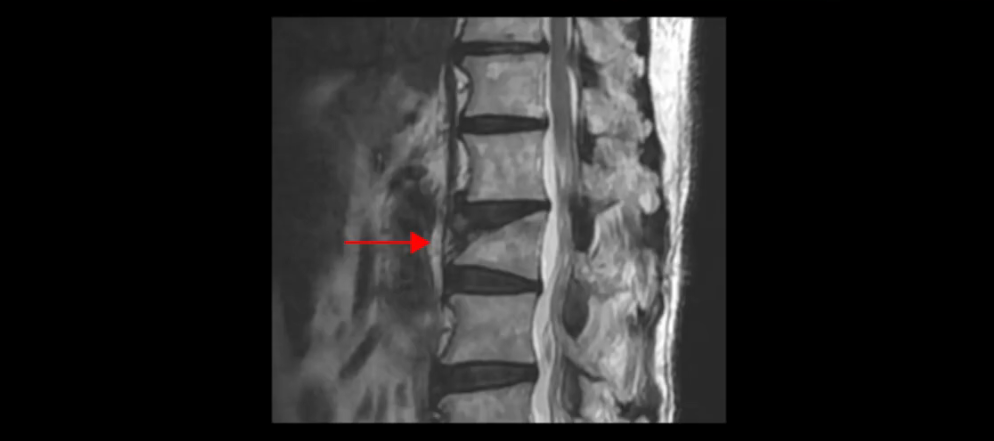

그런데 압박골절은 심하지 않을 경우 그리고 처음에 뼈가 많이 주저 앉지 않는 경우에는 X-ray 소견만으로는 진단이 어려울 수 있습니다. 또 X-ray로는 과거에 발생해서 이미 치유가 된 압박골절과 최근 발생한 압박골절을 구별하기 어렵습니다. 그래서 70, 80대 노인들 중 넘어지고 난 이후 아니면 골다공증이 있는데 갑자기 등이나 허리 부근에서 통증이 심하게 나타난다면 처음부터 MRI 찍어 보는 것이 중요합니다.

MRI는 심하지 않은 압박골절도 진단이 가능하고 기존에 있었던 압박골절과 최근에 발생한 압박골절을 정확하게 구별할 수 있기 때문에 그런 의미에서 압박골절이 의심된다면 처음부터 MRI를 찍어 보는 게 굉장히 중요합니다.